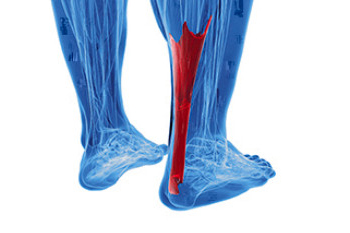

Facts About Achilles Tendon Pain

Achilles tendonitis is a condition that affects the large tendon at the back of the ankle that connects the calf muscles to the heel bone. It develops when the tendon becomes irritated from repeated strain or overuse during activities like walking, running, or jumping. Symptoms include pain, stiffness, swelling, and difficulty pushing off the foot, especially after rest. There are two types, based on where the tendon is affected, either in the middle or near the heel. Risk factors include tight calf muscles, sudden increases in activity, aging, and wearing poor-fitting shoes. A podiatrist can evaluate the tendon, check foot structure, and order imaging to confirm the diagnosis. Treatment may include bracing, orthotics, or surgery if the tendon is damaged. If you have symptoms of Achilles tendonitis, it is suggested that you make an appointment with a podiatrist for a diagnosis and treatment.

Achilles tendon injuries need immediate attention to avoid future complications. If you have any concerns, contact Brian D. Jackson, DPM of Neuhaus Foot and Ankle. Our doctor can provide the care you need to keep you pain-free and on your feet.

What Is the Achilles Tendon?

The Achilles tendon is a tendon that connects the lower leg muscles and calf to the heel of the foot. It is the strongest tendon in the human body and is essential for making movement possible. Because this tendon is such an integral part of the body, any injuries to it can create immense difficulties and should immediately be presented to a doctor.

There are various types of injuries that can affect the Achilles tendon. The two most common injuries are Achilles tendinitis and ruptures of the tendon.

Achilles Tendinitis Symptoms

- Inflammation

- Dull to severe pain

- Increased blood flow to the tendon

- Thickening of the tendon

Rupture Symptoms

- Extreme pain and swelling in the foot

- Total immobility

Treatment and Prevention

Achilles tendon injuries are diagnosed by a thorough physical evaluation, which can include an MRI. Treatment involves rest, physical therapy, and in some cases, surgery. However, various preventative measures can be taken to avoid these injuries, such as:

- Thorough stretching of the tendon before and after exercise

- Strengthening exercises like calf raises, squats, leg curls, leg extensions, leg raises, lunges, and leg presses

What are Achilles Tendon Injuries

The Achilles tendon is the strongest tendon in the human body. Its purpose is to connect the lower leg muscles and calf to the heel of the foot. This tendon is responsible for facilitating all types of movement, like walking and running. This tendon provides an enormous amount of mobility for the body. Any injuries inflicted to this tissue should be immediately brought up with a physician to prevent further damage.

The most common injuries that can trouble the Achilles tendon are tendon ruptures and Achilles tendinitis. Achilles tendinitis is the milder of the two injuries. It can be recognized by the following symptoms: inflammation, dull-to-severe pain, increased blood flow to the tendon, thickening of the tendon, and slower movement time. Tendinitis can be treated via several methods and is often diagnosed by an MRI.

An Achilles tendon rupture is trickier to heal, and is by far the most painful injury. It is caused by the tendon ripping or completely snapping. The results are immediate and absolutely devastating, and will render the patient immobile. If a rupture or tear occurs, operative and non-operative methods are available. Once the treatment begins, depending on the severity of the injury, recovery time for these types of issues can take up to a year.

Simple preventative measures can be taken as a means to avoid both injuries. Prior to any movement, taking a few minutes to stretch out the tendon is a great way to stimulate the tissue. Calf raises, squats, leg curls, leg extensions, leg raises, lunges, and leg presses are all suggested ways to help strengthen the lower legs and promote Achilles tendon health.

Many problems arise among athletes and people who overexert themselves while exercising. Problems can also happen among those who do not warm up properly before beginning an activity. Proper, comfortable shoes that fit correctly can also decrease tendon injuries. Some professionals also suggest that when exercising, you should make sure that the floor you are on is cushioned or has a mat. This will relieve pressure on the heels. A healthy diet will also increase tendon health.

It is very important to seek out a podiatrist if you believe you have an injury in the Achilles region. Further damage could result in severe complications that would make being mobile difficult, if not impossible.